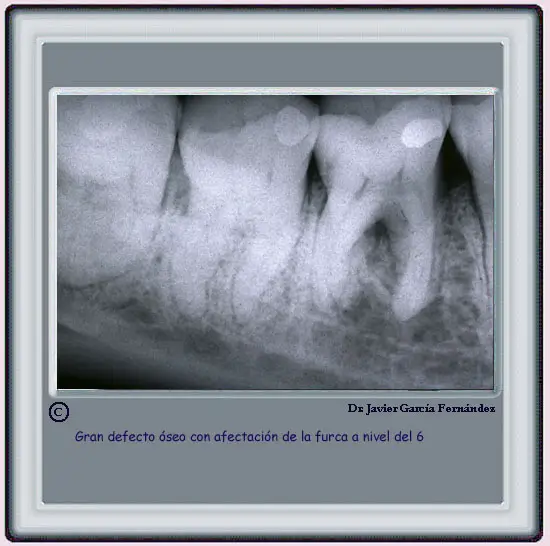

EXAMEN RADIOLÓGICO

image214